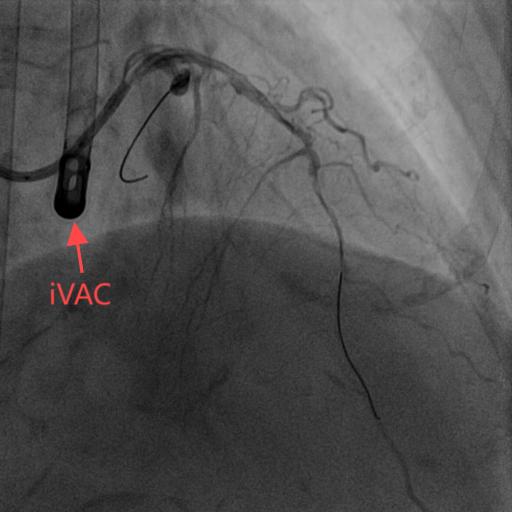

左室辅助装置图像

翟光耀主任带领高鹏副主任医师、陈文明主治医师在左室辅助装置的保护下成功对徐奶奶的前降支施行支架植入术。在经过几天康复后,徐奶奶可以正常下床活动,身体恢复良好,于近日顺利出院了。